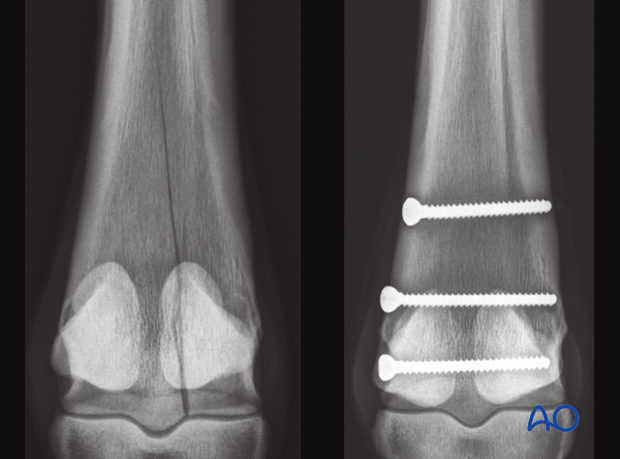

The major principle involved in standing lag screw fixation of these fractures is compression of the articular surface.The fixation of the distal portion of the bone may help prevent proximal propagation of the fracture, but definitely does not prevent it.

Although the glide hole is typically drilled through the smaller fragment and the thread hole across the larger fragment, this particular fracture is often repaired in the opposite manner. The major reason is that it is much safer and easier to approach the leg from the lateral side than the medial side. Fortunately, medial condylar fractures tend to be close to the midline so there is little difference between the width of the two fragments. The bone in this location is so strong that 25 mm of thread engaged with a 4.5 mm cortex screw is already exceeding the strength of the screw. Therefore, strong fixation can be achieved even though the repair is called “backward” or “reverse” lag screw.

A second screw is placed approximately 2 cm proximal to the first screw.

Additional screws may be added according to the radiographically visible length of the fracture. In standing horses, however, most surgeons place only 2-3 screws.